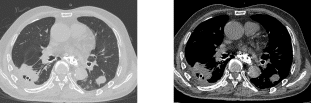

术前胸部CT(肺窗) 纵膈窗